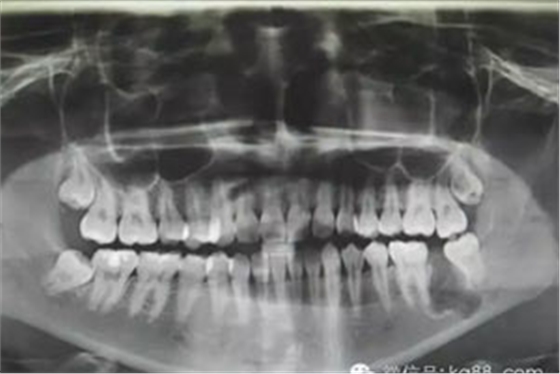

患者、薛xx、女、22歲。主訴:左側(cè)下后牙咬東西不適數(shù)年。??茩z查:37未萌出,36正常萌出,且咬合關(guān)系良好。38近中移位,輕度傾斜,48與27有咬合關(guān)系。37頰側(cè)未能捫及隆起及波動(dòng)感,也未能探及盲袋。x線片檢查:37低位近中埋伏阻生,牙冠周圍有牙囊影。CBCTj檢查:牙冠周圍有囊性改變,診斷:37含牙囊腫。處理:建議手術(shù)拔除37?;颊咄馐中g(shù)。術(shù)前簽知情同意書。

圖1.術(shù)前患者的全景片影像檢查情況:37未萌出,牙冠周圍有囊性陰影,牙根接近下頜骨皮質(zhì)骨邊緣。